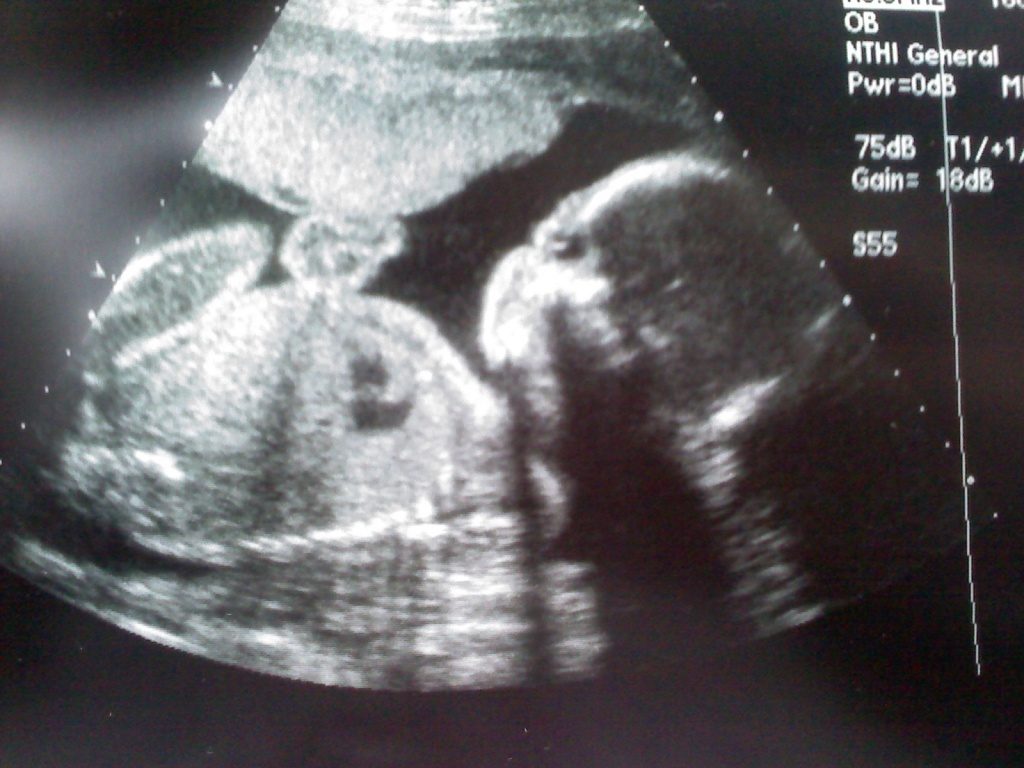

Во время планового осмотра врач, при помощи ультразвукового исследования, определит половые признаки и сообщит эту долгожданную новость родителям. С аппарата УЗИ можно сделать фото младенца, которые сохранят в памяти этот радостный момент.

Проведение ультразвукового исследования в этот период совершенно безопасно для малыша. Эта неделя позволяет вовремя выявить возможные осложнения. Во время УЗИ проверяется соответствие размеров плода необходимым для этого этапа развития параметрам.

Проводится осмотр внутренних органов, и распечатывается фото диаграммы работы сердца. Если по результатам УЗИ видно, что малыш еще не занял правильной позиции головой вниз, не стоит беспокоиться.

У него еще есть достаточное количество времени и пространства, чтобы перевернуться.

На таком сроке беременности может проводиться ультразвуковое исследование плода, и основной его задачей считается исключение патологии развития плода, а также диагностика его общего состояния. При проведении УЗИ специалист может оценить размеры плода, их соответствие предполагаемому сроку беременности, послушать биение сердца и оценить двигательную активность малыша.

Наверняка, во время исследования многие родители захотят узнать, кто же у них родится — мальчик или девочка. На самом деле, на 23 неделе беременности уже хорошо заметны половые признаки плода, и при удачном расположении малыша можно успешно определить его пол.

Во время УЗИ специалист выполняет осмотр внутренних органов плода, оценивает соотношение его отдельных частей тела и их пропорции по отношению друг к другу.С помощью таких показателей удается исключить различные пороки развития малыша и убедиться в отсутствии каких-либо хромосомных аномалий.

УЗИ на 23 неделе беременности позволяет оценить состояние детородного органа и его размер, а также убедиться в правильности расположения плаценты. Для некоторых женщин неприятным известием становится тот факт, что плацента расположена слишком низко. На самом деле, сильно расстраиваться не стоит, ведь в последующем за счет роста матки плацента начнет подниматься и займет нужное положение.

На 23 неделе уже можно узнать пол ребенка

Делая УЗИ на 23 неделе можно увидеть, как плод двигается: он может кувыркаться и хвататься ручками за пуповину, играться с ножками и ручками. Сейчас не только активно развиваются все его органы, но и происходит закладывание строения костей. Хорошо заметны коготки на пальчиках и волосики. Благодаря УЗ-приспособлениям можно отчетливо слышать, как бьется сердечко.

Что видно на фото плода?

Если положение плода позволит, то на фото в 23 недели можно рассмотреть мошонку у мальчика и яичники у девочки.

Также на снимке можно четко увидеть количество пальчиков и разглядеть на них ноготки. На лице отлично виден носик, глаза ребенка, если он не спит, будут открыты. Пушковая растительность на теле и на голове начинает темнеть и это тоже хорошо видно.